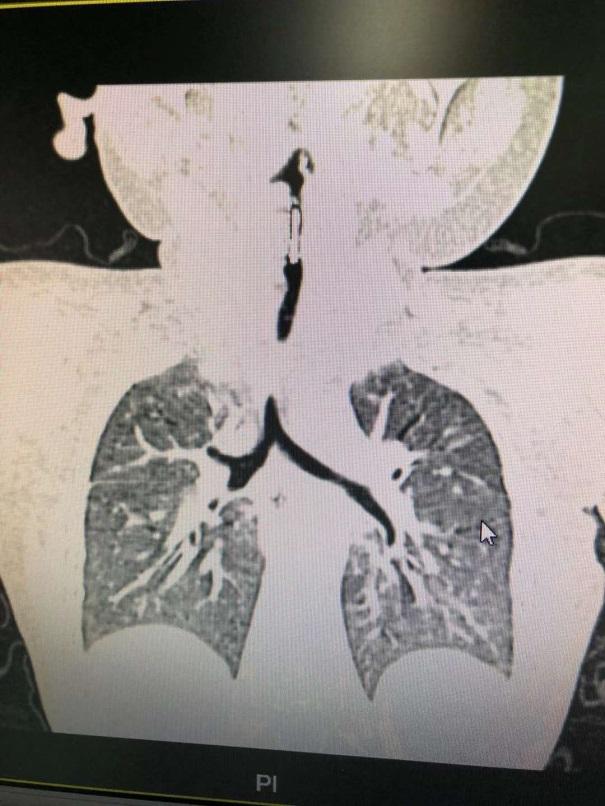

这个孩子出现症状已经整整一个月,之前辗转两家医院,一直被认为是气管炎和哮喘,直到妈妈回忆起当时他曾乱抓东西吃,做了胸部CT才锁定原因:气管异物。